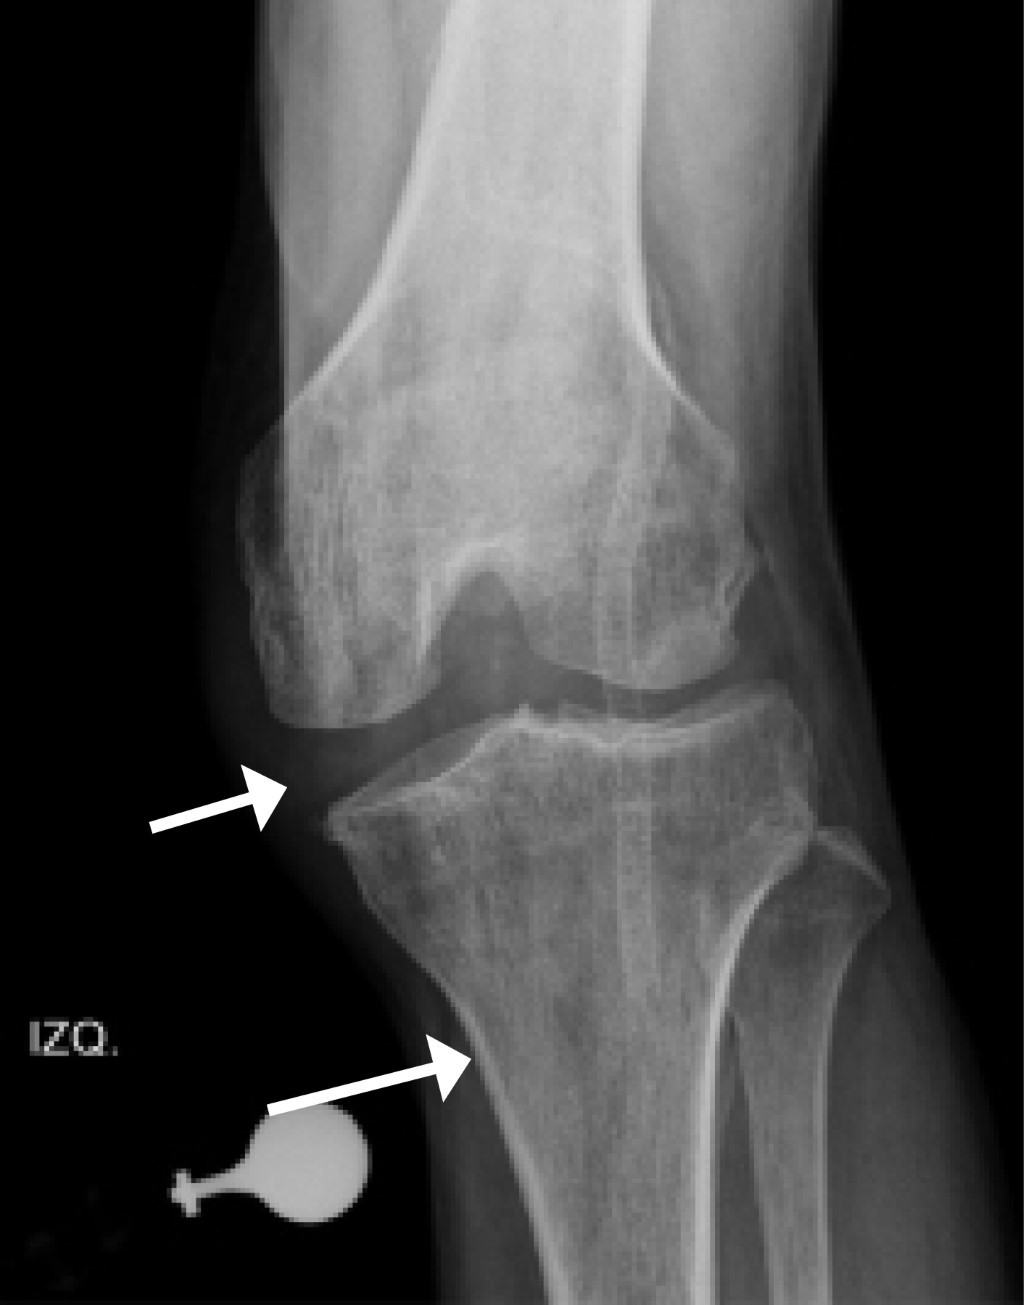

La luxación de rodilla o lesión multiligamentaria de la rodilla, como también se le llama, es una lesión poco frecuente, pero grave debido a que se acompaña en un gran número de ocasiones de lesiones vasculares y nerviosas que requieren un diagnóstico y tratamiento oportuno.1 La luxación implica la pérdida de la congruencia de la articulación tibiofemoral (Figura 1), aunque se debe tener en cuenta que la presentación clínica más común es encontrar la rodilla anatómicamente reducida, pero con inestabilidad importante, que para su definición requiere ruptura de por lo menos dos ligamentos principales.2 Por tradición estas lesiones se han atribuido a impactos de alta energía, aunque recientemente se ha observado en situaciones asociadas a mecanismos de trauma de baja energía, en particular en personas con obesidad mórbida.3

Actualmente las clasificaciones más aplicadas están enfocadas en la identificación y descripción de las estructuras lesionadas y su gravedad para el manejo posterior.21 En 1963 Kennedy fue el primero en clasificar las luxaciones de rodilla según la dirección del desplazamiento tibial en relación con el fémur en anterior (Figura 2A), posterior (Figura 2B), medial, lateral y rotacional.21 Este sistema de clasificación es muy útil para el clínico, en vista de que le permite planear la maniobra de reducción de la rodilla luxada, además de poder alertarlo sobre una posible lesión neurovascular coexistente.21 La principal limitación con este sistema es la variabilidad en los ligamentos lesionados cuando sólo se tiene en cuenta la dirección de la luxación.22

Imagenología: rayos X. El estudio con radiografía simple anteroposterior y lateral en el contexto de la luxación de rodilla se debe dividir en dos escenarios: el primero corresponde al grupo de pacientes que ingresan con una luxación evidente clínicamente, para los cuales las proyecciones AP y lateral son el estudio imagenológico inicial, permitiendo evaluar la dirección de la luxación según la clasificación de Kennedy y así definir el riesgo estimado de lesión vascular, según sea cada caso. Posterior a la realización de las maniobras de reducción es necesario efectuar nuevas proyecciones AP y lateral que permitan evaluar adecuadamente las relaciones de la articulación tibiofemoral en búsqueda de subluxaciones residuales y la presencia de lesiones asociadas (Figura 3).38,39

El segundo escenario es mucho más complejo de abordar, se presenta cuando el paciente ingresa al servicio de urgencias con la rodilla reducida, haciendo del diagnóstico de la luxación de rodilla un reto para el clínico, en el cual las radiografías iniciales tienen un papel valioso en la evidencia de hallazgos característicos que pueden sugerir el diagnóstico de luxación como la apertura de los espacios articulares tibiofemorales (Figura 4), fracturas del cóndilo femoral, fracturas de espinas tibiales anterior y posterior, signo del ligamento arcuato (Figura 5) o el signo de Segond (Figura 6).3

Figura 1

Figura 2